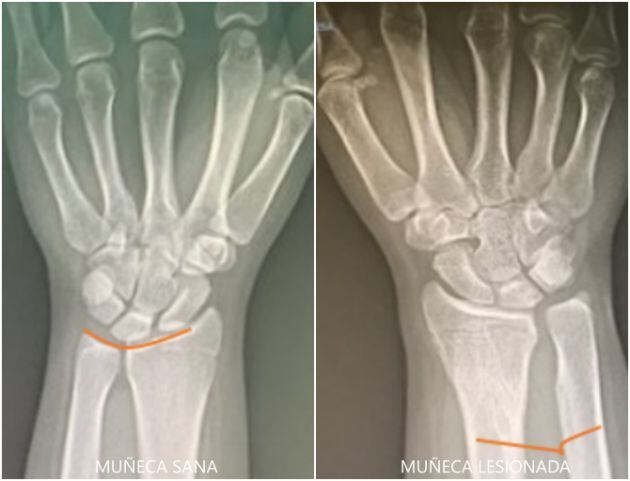

Un ejemplo reciente tratado en Quironsalud Alicante es el caso de una paciente de 16 años que acude a la consulta por dolor en su muñeca que le limita sus actividades diarias como consecuencia de una fractura sufrida 4 años antes.

Mediante la impresión de un modelo 3D se pudo valorar la lesión, decidir el tratamiento más adecuado (un acortamiento del cúbito y una reinserción del menisco mediante artroscopia) y planificar todo el procedimiento.